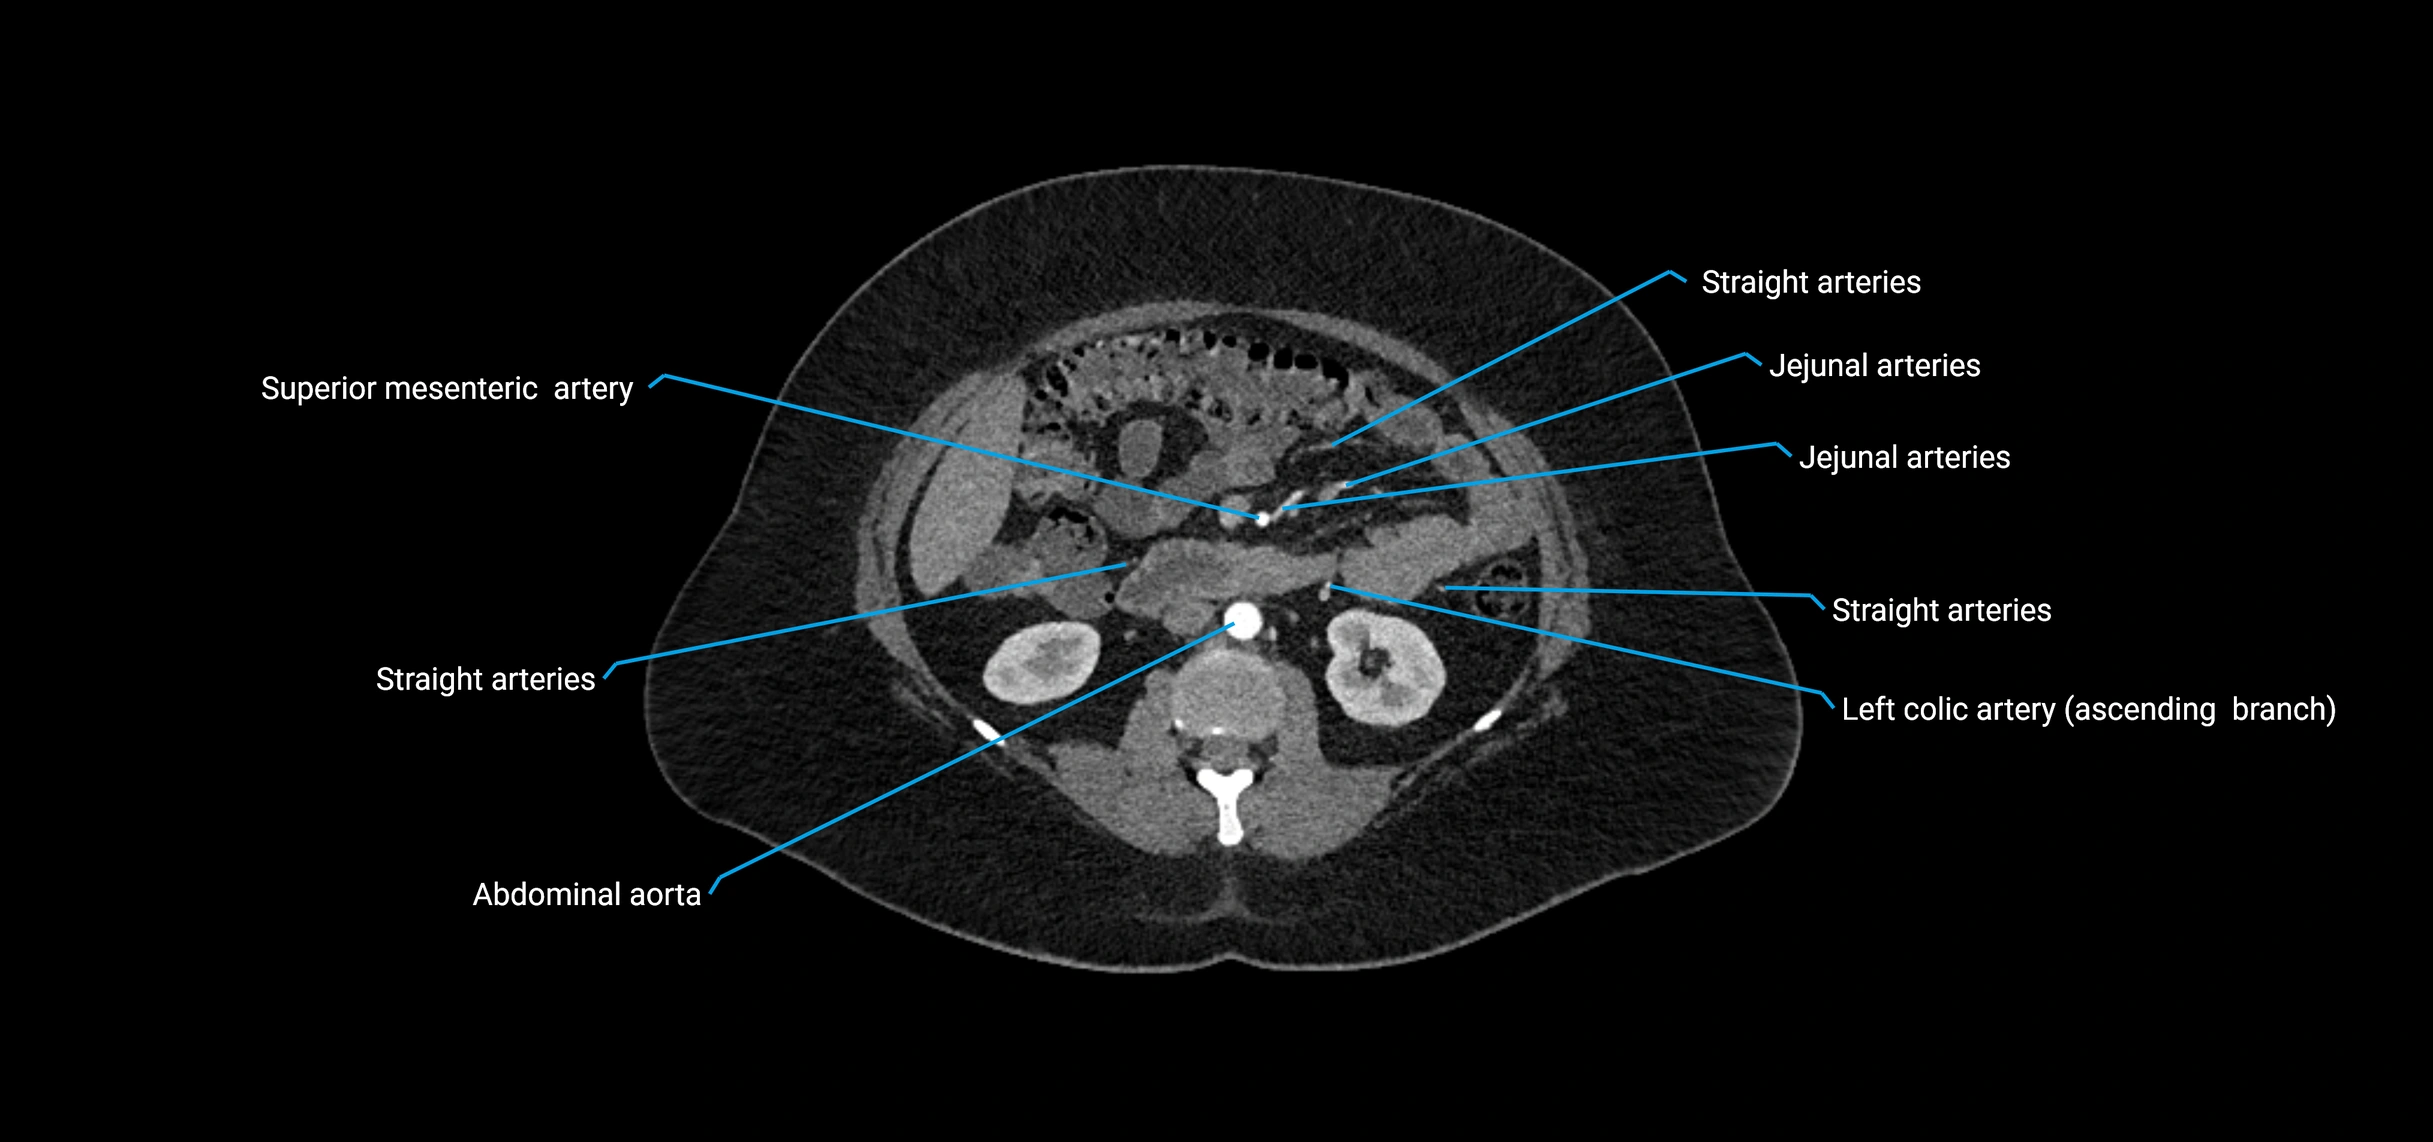

Contrast-enhanced CT (CTA):

• Gold standard for abdominal aortic imaging

• Provides excellent detail of lumen, wall, aneurysm, thrombus, and branch vessels

• Multiplanar and 3D reconstructions help in aneurysm measurement, stent graft planning, and dissection evaluation